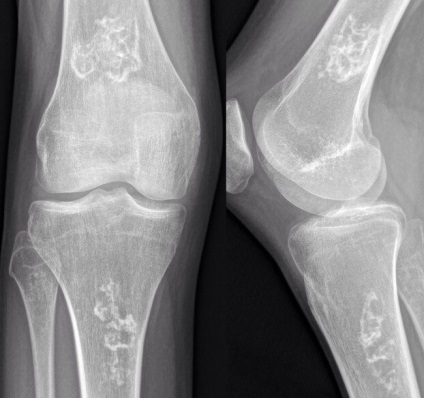

semne radiografice de infarct osos

În stadiu incipient - osteopenia si pierderea de os trabecular cu inelul din jurul sclerotic

Loturi scleroză, format în zona de necroză osoasă și formarea unui os nou relativ

In etapa ulterioara - porțiunile inegale întunecare sau calcifiere (sub formă de pietricele imagini marine, ciorchini de struguri sau inel țintă), situat în mod normal, la periferie

in zona de infarct osos poate avea o lungime de până la 20 cm

Atunci când o regiune miocardică în epifizei sau în formă de pană limba-black-out se extinde de la baza epifizei la suprafata articular.